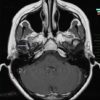

U dây VIII

» Thông tin: Nữ giới – 35 tuổi.

» Lâm sàng: Điếc đột ngột.